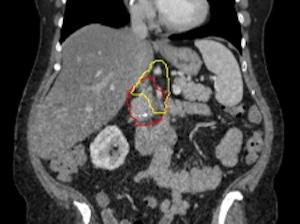

Image of a what is targeted with radiation. Red represents the pancreatic tumor, which is contacting with a major nearby artery. Yellow represents the Baltimore Triangle, which is now targeted in all patients, in addition to red volume. (Credit: Amol Narang, M.D.)

The team learned that the pancreatic cancer cells were spreading along nerves near the pancreas to a fatty, nerve-dense triangular area just above the pancreas, which Narang calls the “Baltimore triangle.” When he and his colleagues started targeting the Baltimore triangle with radiation before surgery to kill these stray cancer cells, pancreatic cancer recurrence rates in their patients dropped from 47% to 12% at two years post-surgery. Yet, in the 12% who experienced recurrences around the pancreas, the recurrences continued to occur in the Baltimore triangle.

To further lower recurrence rates, Narang and his colleagues decided to deliver an additional round of Baltimore triangle-targeted radiation to patients during surgery after removal of the pancreatic tumor. He explained that, during the surgery, surgeons remove a part of the small intestine next to the pancreas — called the duodenum — making it easier to access the Baltimore triangle without risking harm to surrounding organs. The combination of radiation targeted to the Baltimore Triangle prior to surgery as well as intraoperative radiation to the triangle during surgery allowed Narang to deliver ablative doses of radiation to this region.